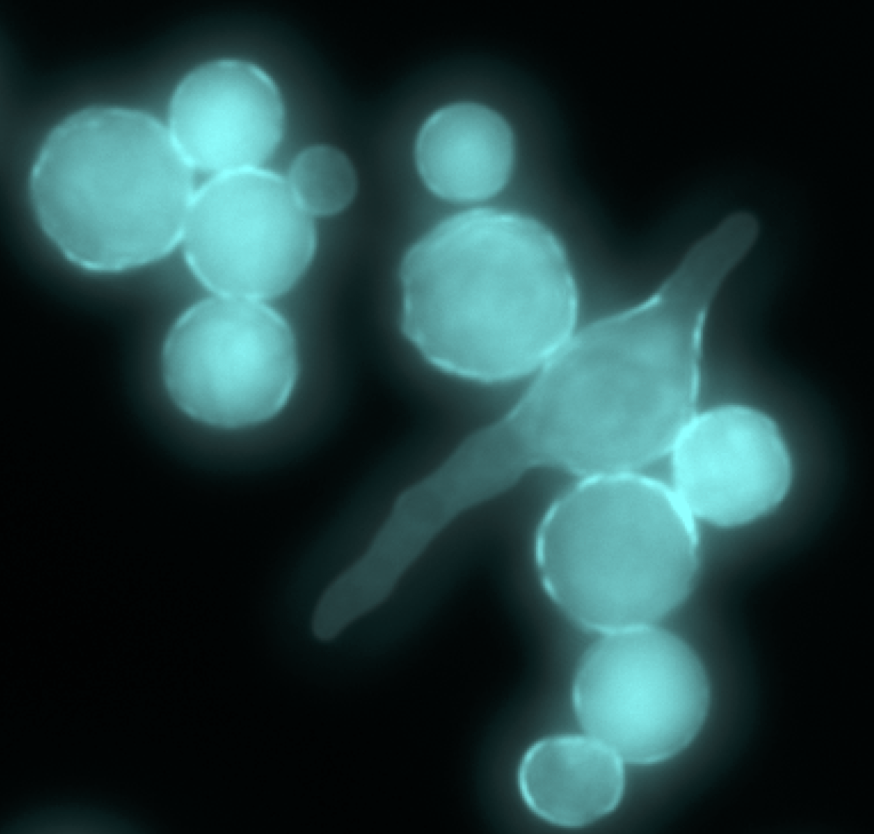

Mucorales species including Rhizopus microsporus and Rhizopus delemar, commonly associated with food spoilage, also cause fatal invasive mucormycosis. Infecting spores escape early immune cell clearance and germinate into invasive hyphae, causing devastating disease.

Work in our group has demonstrated that the ability of Rhizopus spores to germinate and escape clearance is influenced by the presence of bacterial endosymbionts that can impact both fungal host and phagocyte behaviors. We seek to understand this tri-kingdom interaction at both the transcriptional level and in the context of animal infections, including zebrafish and mouse models of infection.